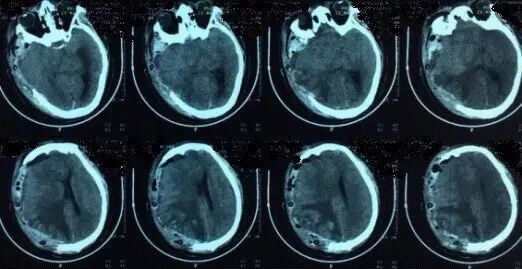

患者,男,40岁;因不明原因反复头痛并加重2月,于2017年4月21日当地医院头颅CT、MRI提示:双侧额颞顶部慢性硬膜下血肿收住院(图1)。并于4月24日行“左侧慢性硬膜下血肿钻孔引流术”。术后患者卧床、静脉补液,头痛症状有所缓解。复查头颅CT显示左侧血肿较前减少,但右侧稍增大(图2)。

图2. 左侧慢性硬膜下血肿钻孔引流术后1天复查头颅CT,显示左侧硬膜下血肿较术前减少。